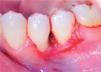

Clinical examination revealed an inflammatory gingival lesion at the level of teeth 3.4 and 3.5. Measuring approximately 15 x 9 mm. The lesion covered the vestibular side of the clinical crown, it was firm, lobulated, of rugged texture and bleeding upon stimulus (Figures 1and2). Periodontal assessment did not reveal periodontal pockets; presence of plaque was observed, and an O’Leary oral hygiene index of 18.75 was determined. Radiographic evaluation revealed absence of interproximal contact between teeth 3.4 and 3.5 as well as restorative material in the interproximal area (Figure 3).